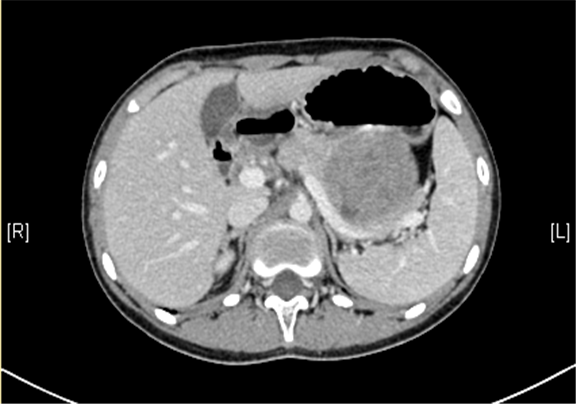

上腹部三维CT动态增强扫描: 胰腺体尾部类圆形软组织肿块,考虑实性假乳头状瘤可能性大。

术前CT检查:

动脉期

静脉期

平衡期